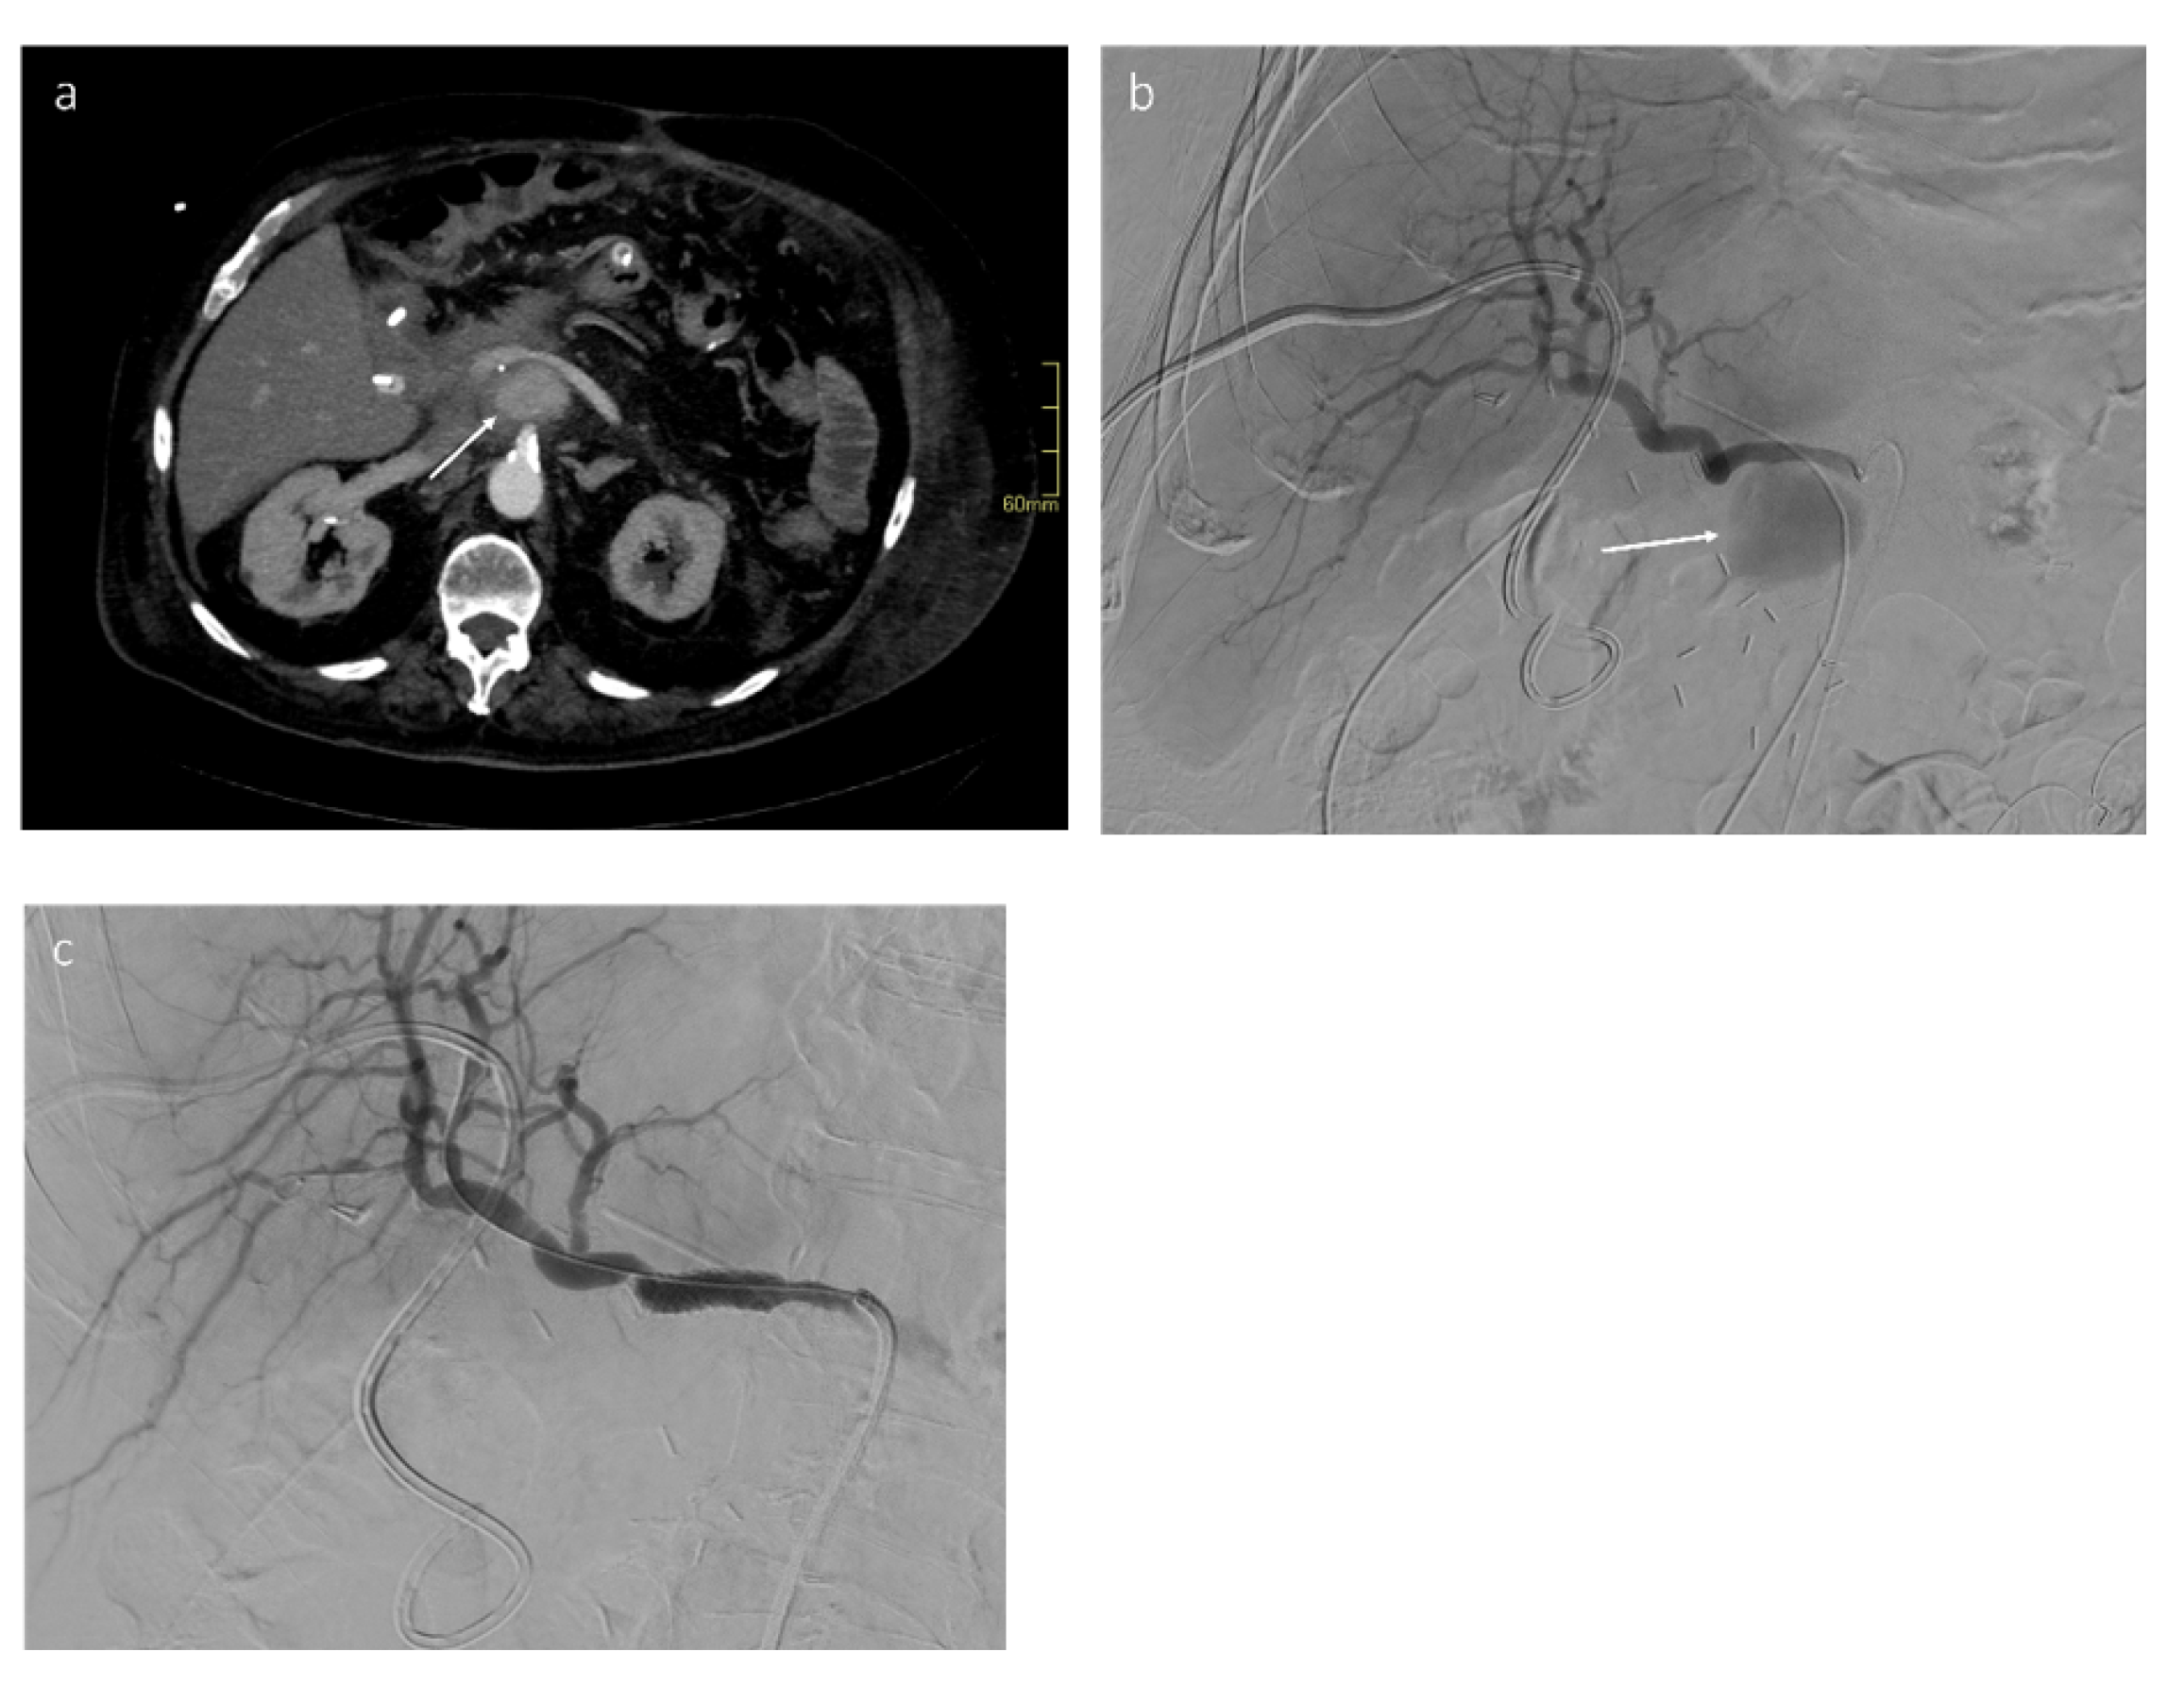

4. Transcatheter Embolization (Stent–Graft)

5. Intra-Portal Islet Auto-Transplantation